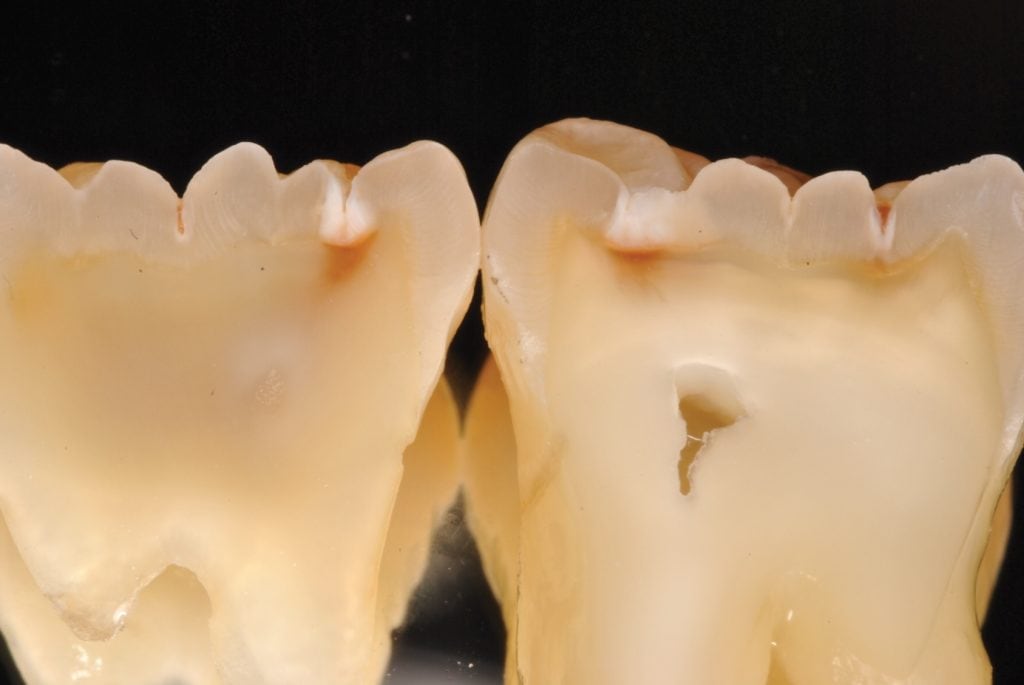

Cavities going into tooth

Cavities in back molar before air abrasion